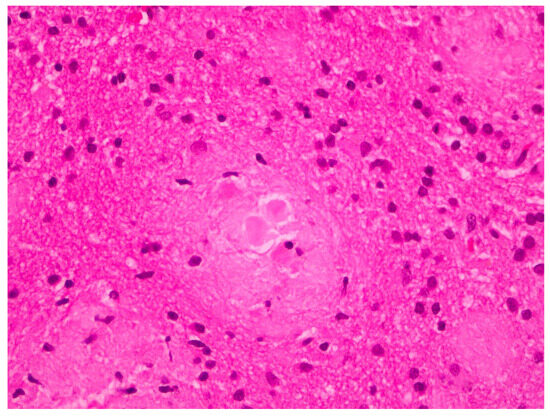

2. Case Report